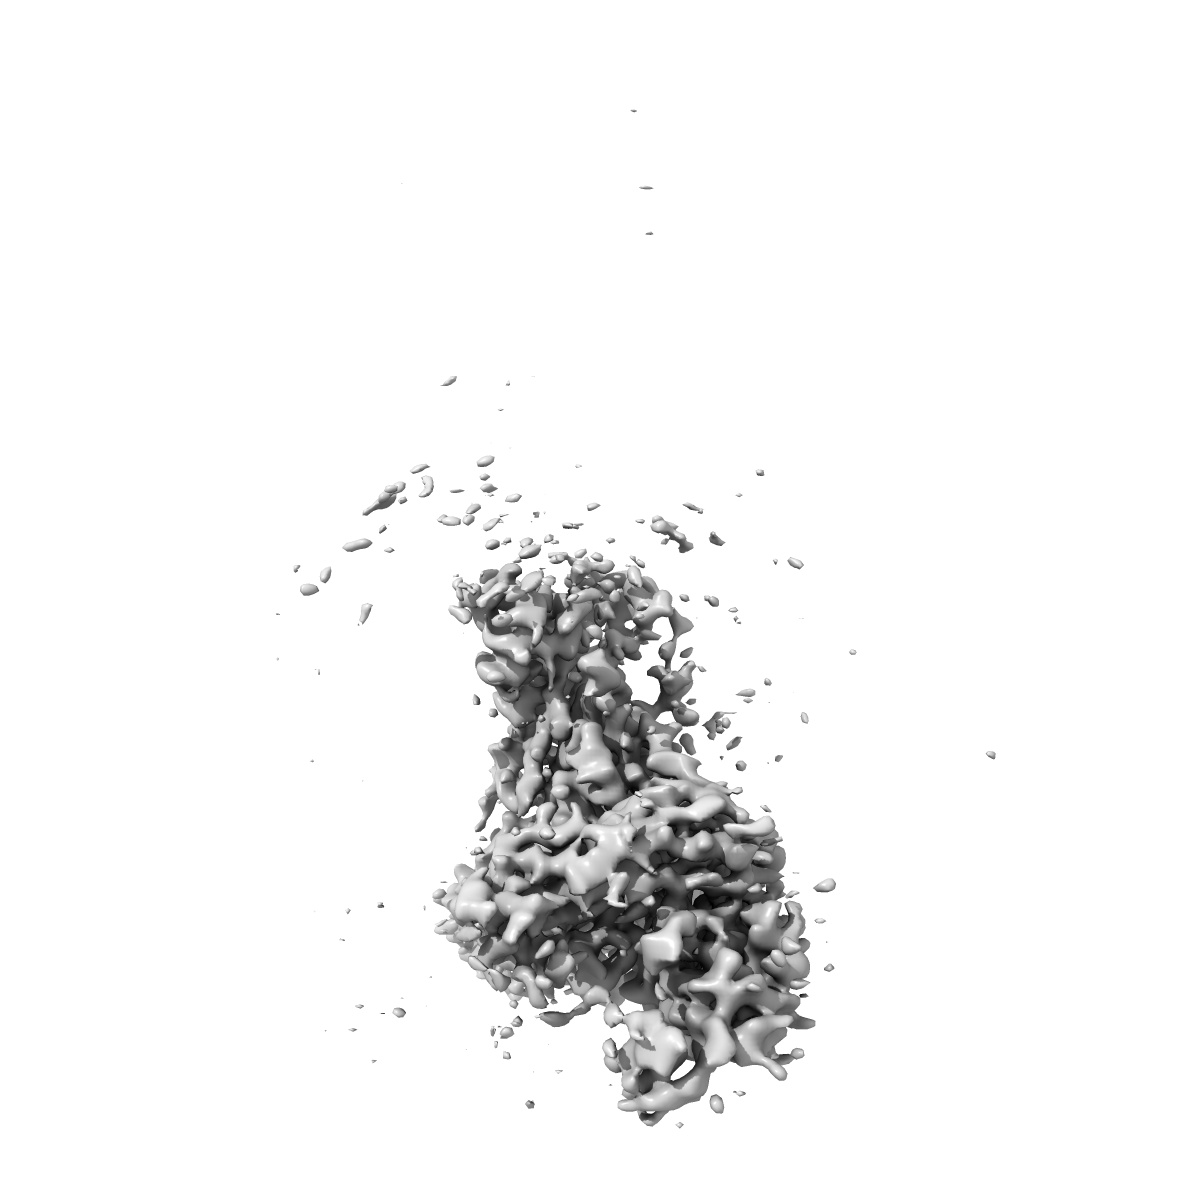

Cryo-EM structure of SARS-CoV-2 spike protein in complex with double nAbs 8H12 and 1C4 (local refinement)

Single-particle3.77 Å

Sample: Cryo-EM structure of SARS-CoV-2 spike protein in complex with 8H12

Two antibodies show broad, synergistic neutralization against SARS-CoV-2 variants by inducing conformational change within the RBD.